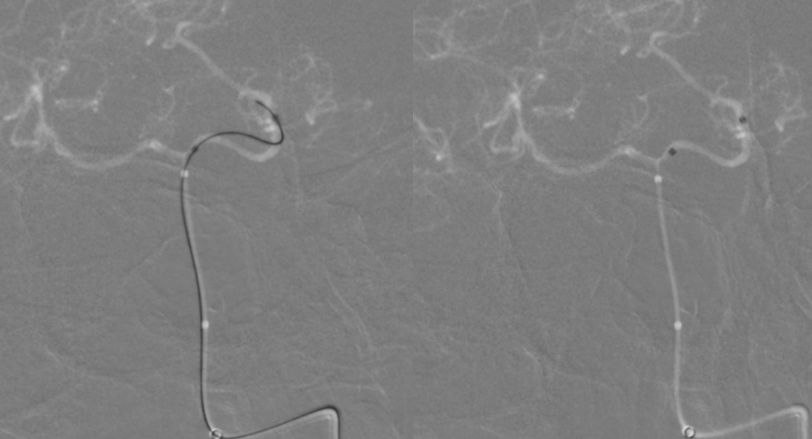

3、多个投射角度辅助下,将一枚3x35 mm的Tubridge支架经T-track支架微导管缓慢释放(图10)。

图10

4、支架完全释放后造影可见支架完全覆盖动脉瘤,贴壁良好,载瘤动脉及支架覆盖的双侧AICA及右侧椎动脉通畅(图11)。

图11